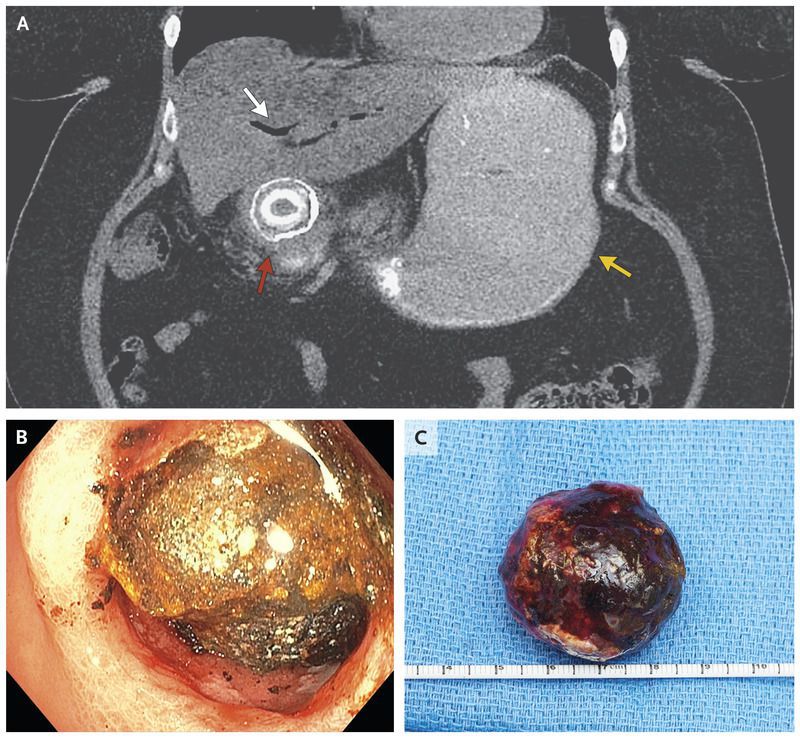

A 57-year-old woman presented to the emergency department with a 2-week history of nausea and vomiting. During the previous month, she had had intermittent episodes of right-upper-quadrant abdominal pain. Abdominal examination revealed a distended abdomen with decreased bowel sounds and mild epigastric tenderness without peritoneal signs. Computed tomography of the abdomen (Panel A) revealed pneumobilia (white arrow), gastric distention (yellow arrow), and a gallstone obstructing the proximal duodenum (red arrow). Bouveret’s syndrome is an uncommon form of gallstone ileus that is characterized by a gastric outlet obstruction caused by impaction of a gallstone in the pylorus or proximal duodenum after its passage through a cholecystoduodenal fistula. Patients with gallstone ileus may present with radiographic findings of Rigler’s triad (i.e., pneumobilia, small-bowel obstruction, and an ectopic gallstone). Mechanical lithotripsy with endoscopic removal of the stone was attempted in the patient (Panel B); however, the procedure was unsuccessful and was complicated by a perforation of the proximal duodenum. The patient then underwent an open laparotomy for repair of the duodenal perforation and removal of a mixed gallstone, which measured 4.4 cm in the greatest dimension (Panel C). She had complete resolution of symptoms and was discharged home 15 days after admission.